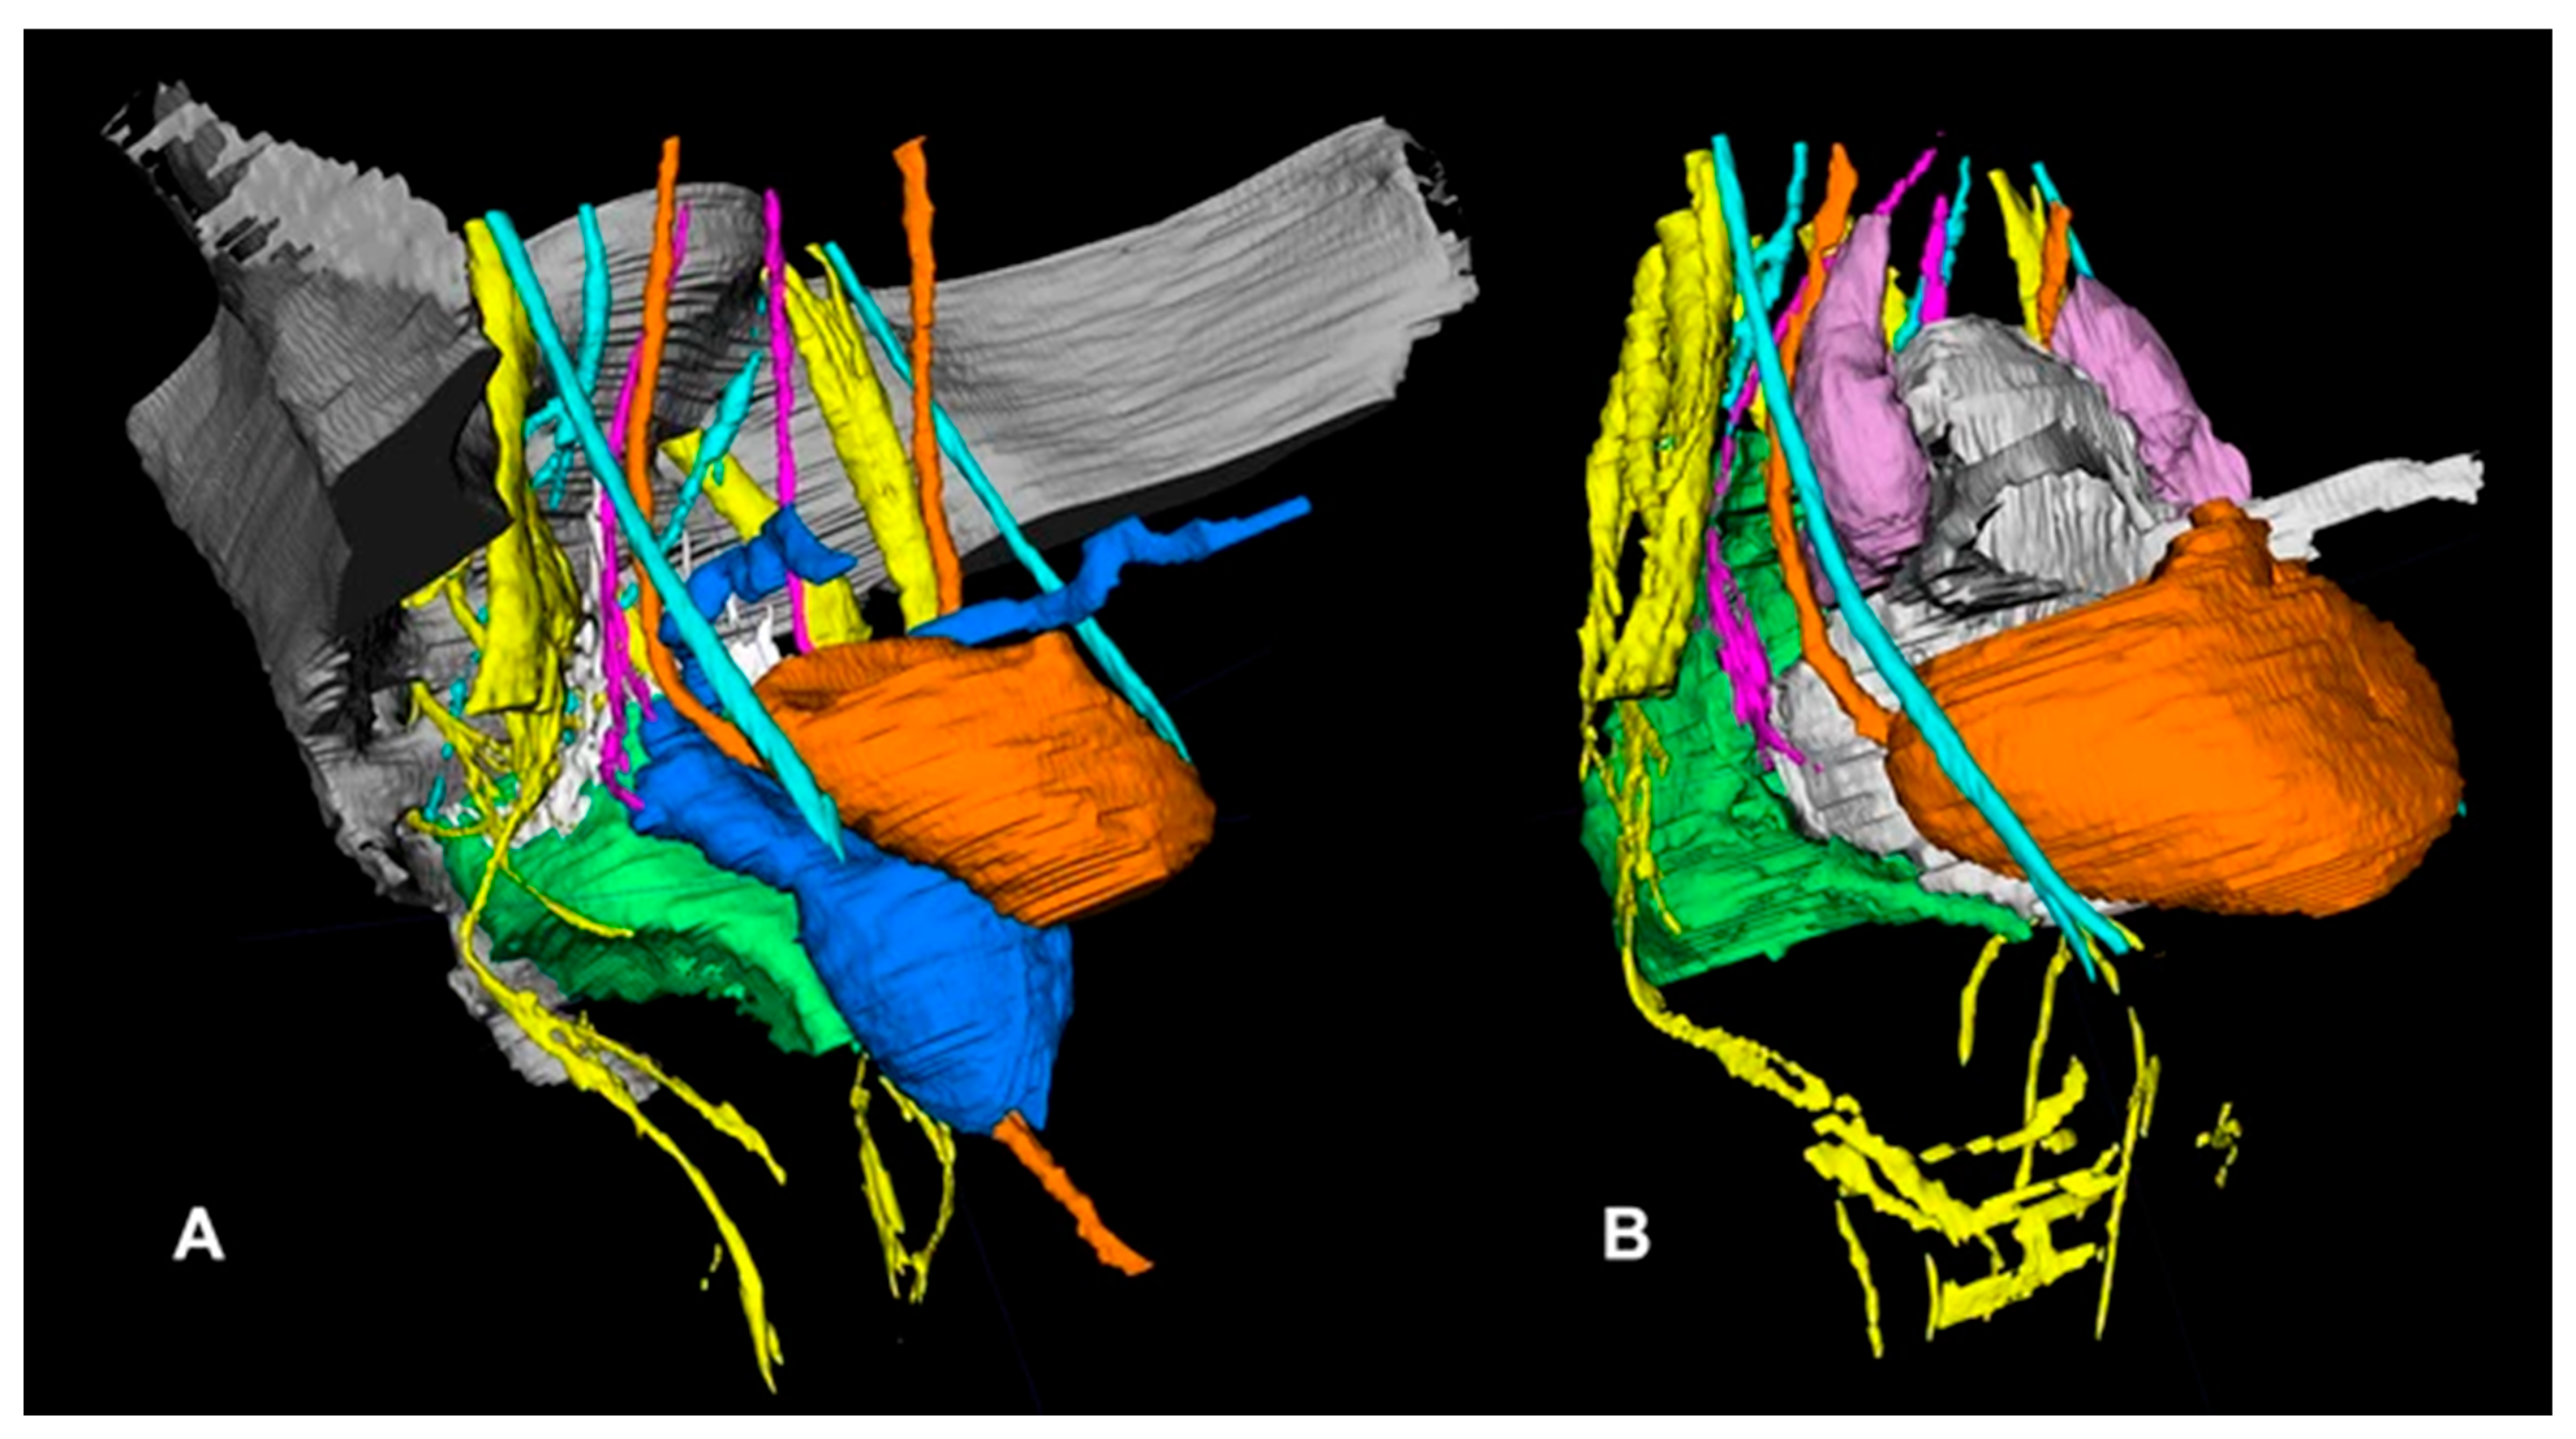

- Wijsmuller, A.R.; Giraudeau, C.; Leroy, J.; Kleinrensink, G.J.; Rociu, E.; Romagnolo, L.G.; Melani, A.G.F.; Agnus, V.; Diana, M.; Soler, L.; et al. A step towards stereotactic navigation during pelvic surgery: 3D nerve topography. Surg. Endosc. 2018, 32, 3582–3591. [Google Scholar] [CrossRef] [PubMed]

- Muller, C.O.; Mille, E.; Virzi, A.; Marret, J.-B.; Peyrot, Q.; Delmonte, A.; Berteloot, L.; Gori, P.; Blanc, T.; Grevent, D.; et al. Integrating tractography in pelvic surgery: A proof of concept. J. Pediatr. Surg. Case Rep. 2019, 48, 101268. [Google Scholar] [CrossRef]

- Bertrand, M.M.; Macri, F.; Mazars, R.; Droupy, S.; Beregi, J.P.; Prudhomme, M. MRI-based 3D pelvic autonomous innervation: A first step towards image-guided pelvic surgery. Eur. Radiol. 2014, 24, 1989–1997. [Google Scholar] [CrossRef]

| Diffusion Tensor Imaging (DTI) | Map directional nerve tracts, 3D reconstruction | Sacral nerves, IHP | [35,61] |

| Stereotactic Navigation | Real-time nerve guidance during TaTME | SHP, HN, IHP, CN | [35,37,61] |